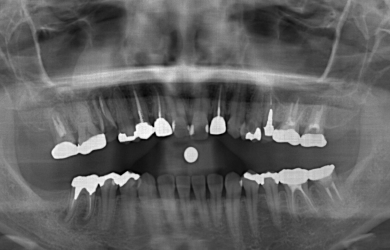

抜歯即日スピードインプラント+ソケットリフト

| 主訴 | 右上奥歯を現在、他の歯科医院にて治療中。歯が割れているとのことで抜歯すると言われたので、何か良い方法がないか相談したい。 | ||||||||||||||||||||||||||||||||

| 治療方針 | 初期固定に必要な骨の量がほとんどないため、ソケットリフト法を併用した抜歯即日スピードインプラントを行ってみるが、初期固定がとれなかった場合には通常の段階的な方法にてまず抜歯を行い、その後4カ月ほど待ち、骨が出来てからインプラント手術を行う。 | ||||||||||||||||||||||||||||||||

| 治療内容 | インプラント1本(抜歯即日スピードインプラント+ソケットリフト)、ハイブリッドセラミック1本、メタルボンドセラミック2本、ハイブリッドセラミックインレー1本 | ||||||||||||||||||||||||||||||||